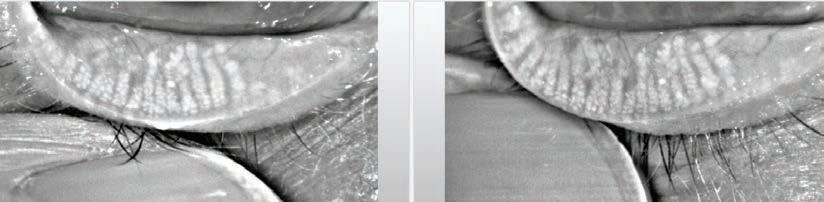

DEMODEX DIAGNOSIS

Cylindrical dandruff at the base of the eyelash is the main clinical presentation of Demodex.12 In

order to observe an individual mite in the clinical setting using a slit-lamp, the lash can be rotated at its base several times using tweezers, (termed the ‘Mastrota rotation’) until its tail emerges partially from the follicle. Another method is to exert ‘lateral tension’ on the lash to observe the emerging tail from the follicle opening without lash epilation.13

CLINICAL PRESENTATION OF OCULAR DEMODEX

The clinical presentation includes itching, especially along the lid margin, swollen eyelids, and ocular discomfort, symptoms typical of blepharitis. Cylindrical dandruff surrounding the base of the lash are pathognomonic of ocular Demodex. Some patients may present with loose lashes, and misdirected lashes or trichiasis due to Demodex infestation that impact nutrients and follicle structure.6 In more severe cases, Demodex can block the openings of follicles and gland ducts, leading to epithelial hyperplasia and hyperkeratinisation.